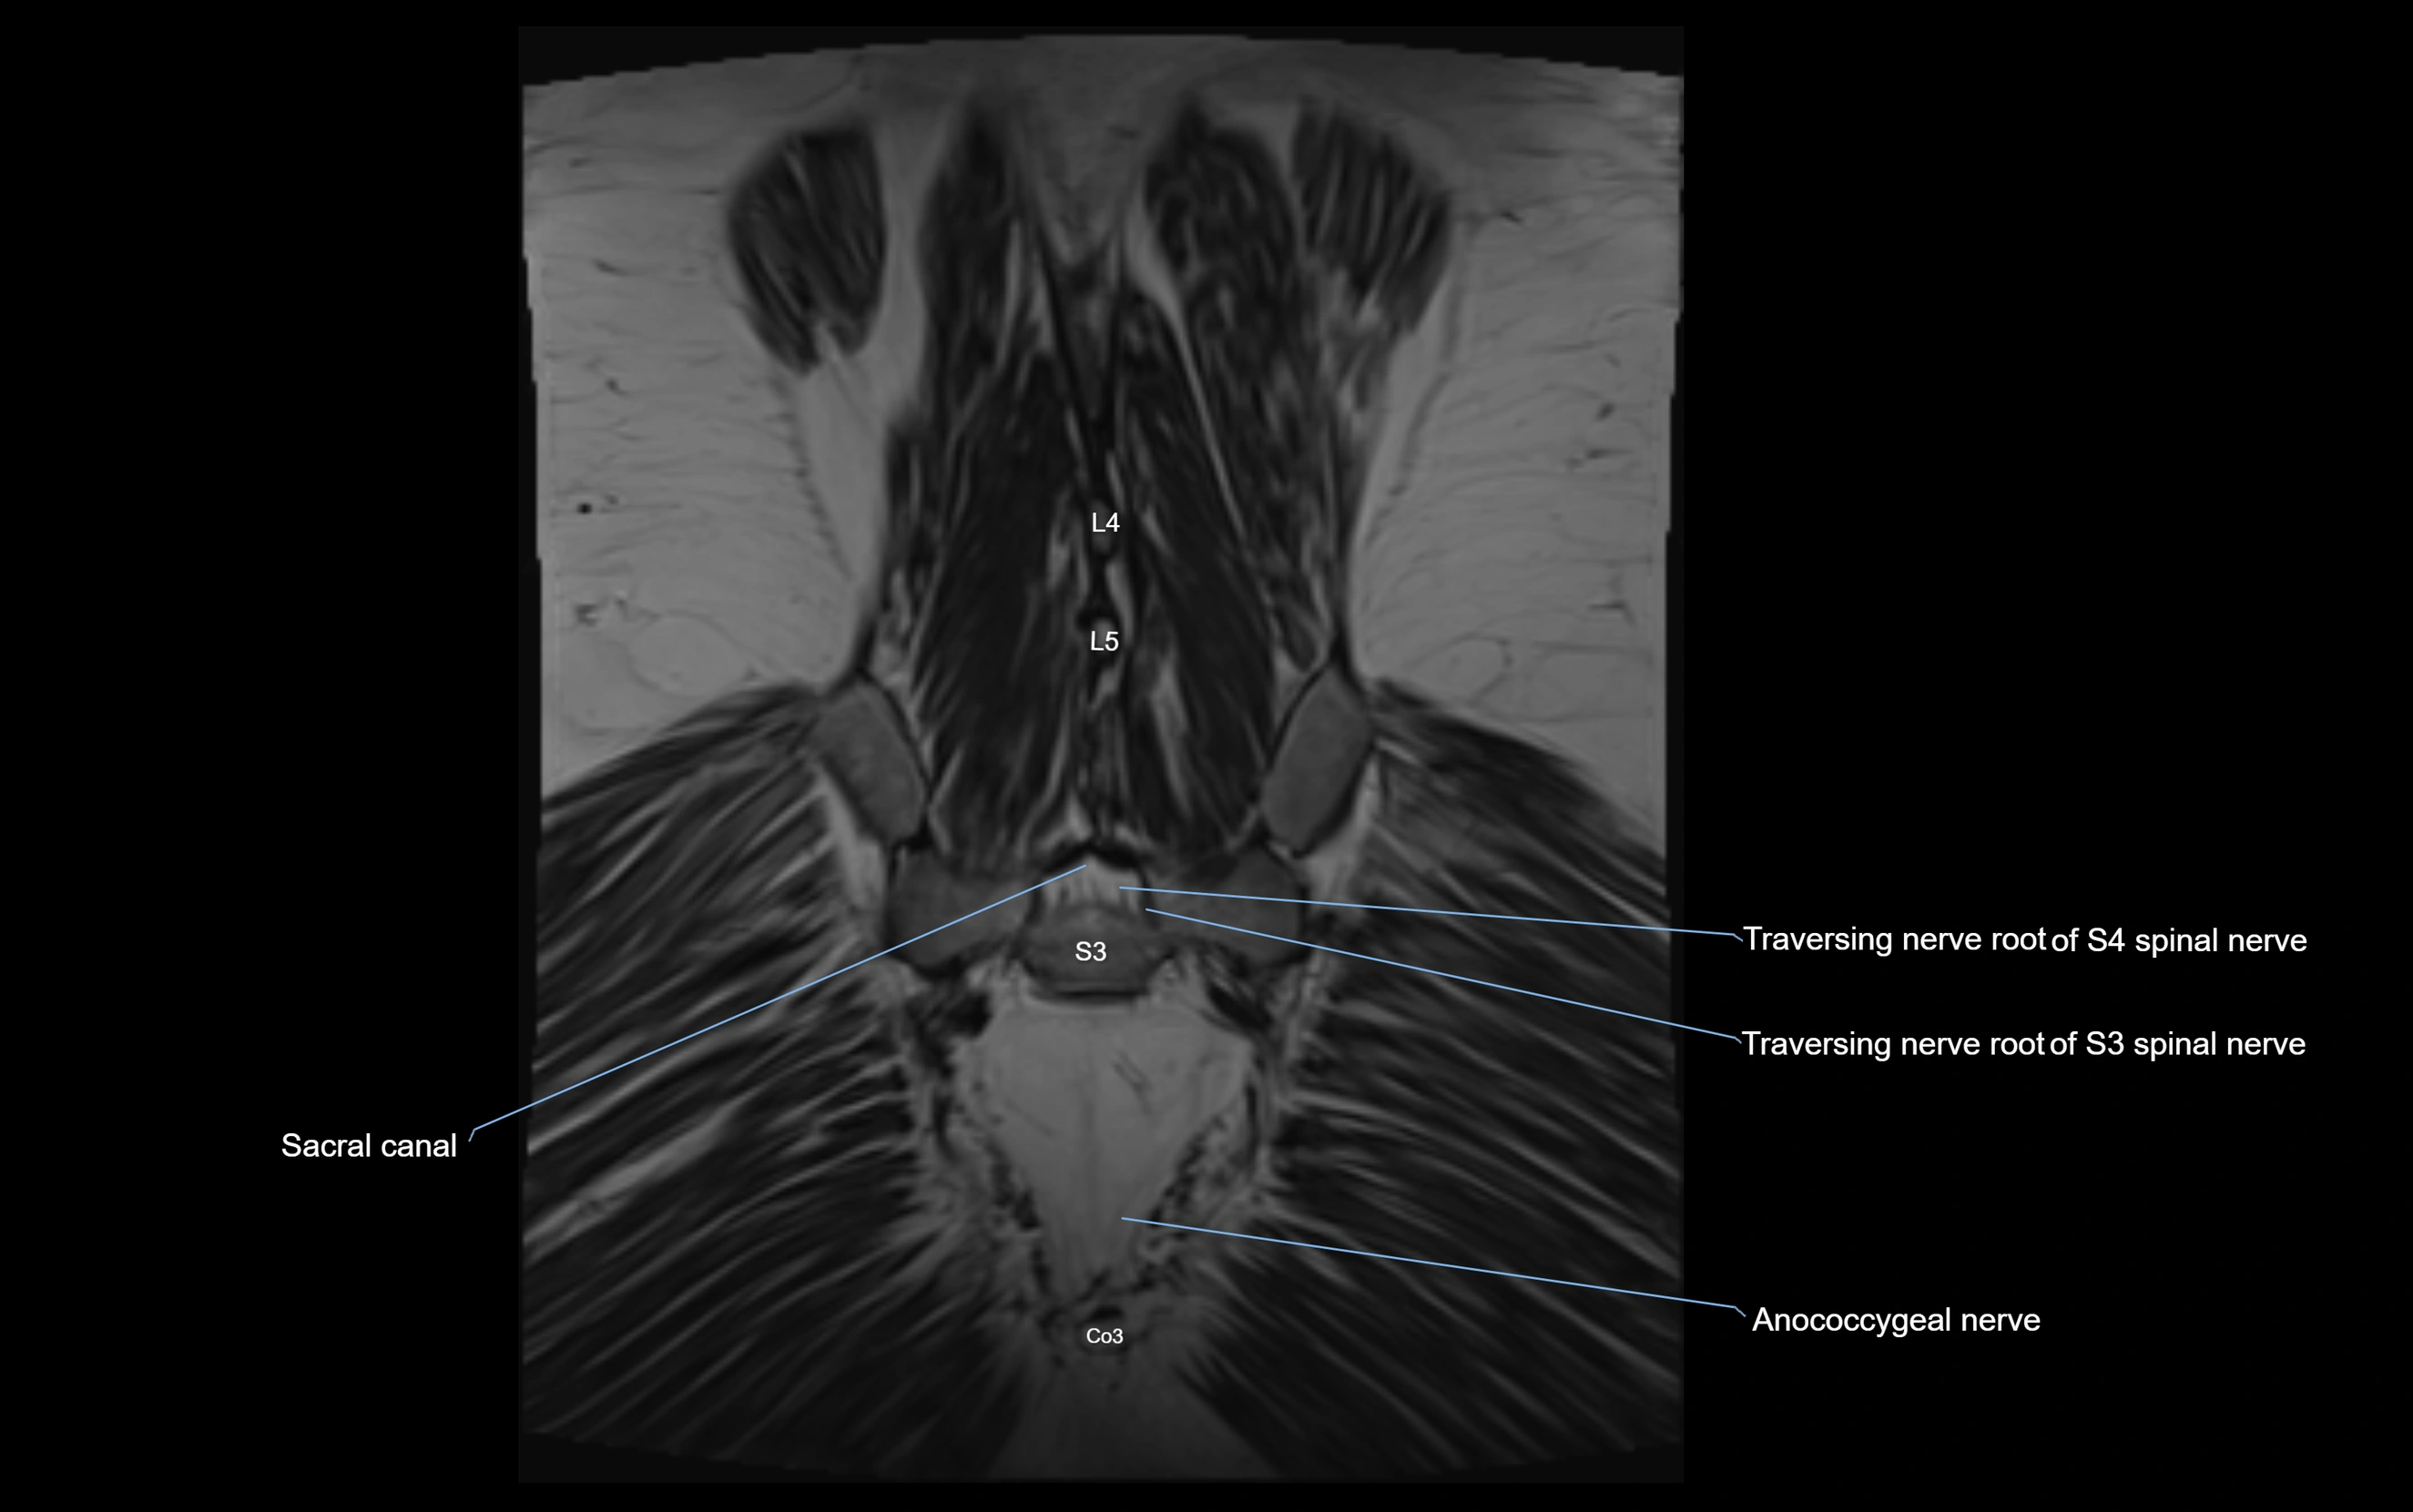

Anococcygeal nerve

The anococcygeal nerve is a small sensory nerve derived from the coccygeal plexus, which itself is formed by the ventral rami of S4, S5, and the coccygeal nerve (Co1). Although tiny, this nerve plays an important role in supplying the skin of the coccyx and the area between the anus and coccyx. It passes through the sacrotuberous ligament and runs in the midline behind the coccyx.

Despite its small size, the anococcygeal nerve is clinically important because of its involvement in coccygodynia (coccyx pain) and perineal pain syndromes.

MRI image

image